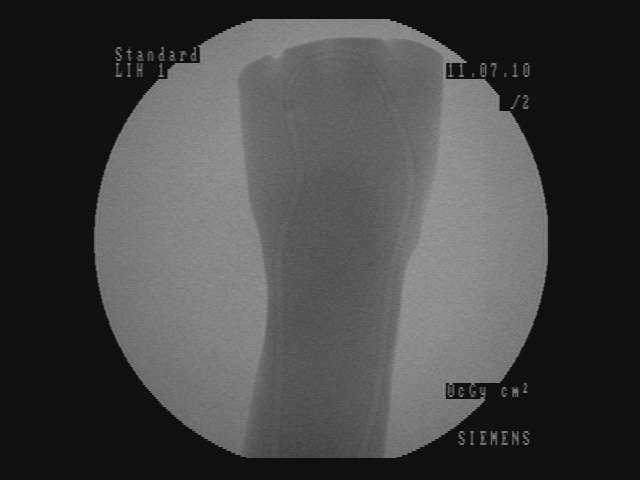

2.3 Visualization results

In Figure 5, for each scenario, one selected image Ilayerssubscript𝐼𝑙𝑎𝑦𝑒𝑟𝑠I_{layers} in the sequence can observed with different values of α𝛼\alpha, β𝛽\beta, γ𝛾\gamma and δ𝛿\delta. Each row i𝑖i corresponds to the sequence i𝑖i. From left to right, the layer visualized in Ilayerssubscript𝐼𝑙𝑎𝑦𝑒𝑟𝑠I_{layers} is getting closer to the X-ray source viewpoint. In the column (a), the furthest layer (the X-ray image) is displayed. In the column (b), the second layer (the background), in the column (c), the blending of the front layer with the background, in the column (d), the blending of the three layers and finally, in the column (e), the closest layer is shown. Additional images from the sequences can be visualized in the supplementary video where interaction between the layers by changing the blending values can be observed.

Despite the fact that the background cannot be ideally recovered, a manual post processing step involving inpainting is applied and displayed in the column (f) of Figure 5. We believe that the multi-layer visualization concept is an interesting and profound solution offering numerous possibilities in the surgical areas, as well as, the mixed reality communities.

(a) (α,β,γ,δ)=(0,0,1,1)𝛼𝛽𝛾𝛿0011(\alpha,\beta,\gamma,\delta)=(0,0,1,1)

Refer to caption

(b) (α,β,γ,δ)=(0,1,0,0)𝛼𝛽𝛾𝛿0100(\alpha,\beta,\gamma,\delta)=(0,1,0,0)

(c) (α,β,γ,δ)=(0.4,0.6,0,0)𝛼𝛽𝛾𝛿0.40.600(\alpha,\beta,\gamma,\delta)=(0.4,0.6,0,0)

(d) (α,β,γ,δ)=(0.2,0.3,0.5,0.5)𝛼𝛽𝛾𝛿0.20.30.50.5(\alpha,\beta,\gamma,\delta)=(0.2,0.3,0.5,0.5)

(e) (α,β,γ,δ)=(1,0,0,0)𝛼𝛽𝛾𝛿1000(\alpha,\beta,\gamma,\delta)=(1,0,0,0)

(f) Inpainting

Figure 5: Per row i𝑖i, multi-layer image Ilayerssubscript𝐼𝑙𝑎𝑦𝑒𝑟𝑠I_{layers} of one selected frame in the sequence i𝑖i with different blending parameters (α,β,γ,δ)𝛼𝛽𝛾𝛿(\alpha,\beta,\gamma,\delta)

Similar to results from Habert et al. [6], the images resulting from synthesization are not as sharp as a real video image. The area synthesized by our algorithm is approximately 20 cm ×\times 20 cm (C-arm detector size), which is small compared to the wide-angle field of view from the Kinect v2. Reduced to the area of synthesization, the video and depth from Kinect is not of high resolution enough for sharper results. More specialized hardware with smaller field of view and higher resolution RGBD data would solve this problem. Moreover, several artifacts can be seen around the hand and surgical instruments in the synthesized image due to high difference and noise in depth in the RGBD data from the 2 cameras. However, our results demonstrate that our method is working well, since the incision line and cross drawn on the hand model and patient hand are perfectly visible in the recovered background image and can be seen in transparency through the hands and surgical tools in the images of Figure 5-column (c) and (d). In the scalpel sequence (sequence 6) in Figure 5-column (b), it can be seen that the tip of the scalpel is considered as background, this is due to the margin of few centimeters used for background segmentation. In this image, the scalpel is actually touching the skin.